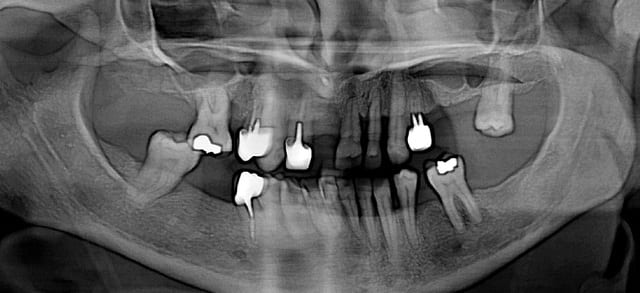

je reçois actuellement une patiente qui a une parodontite en phase terminale.

Voulant la conseiller au maximum, je voudrai vous demander votre avis pour un traitement parodontal au laser suivi d'une greffe osseuse (si possible).

(désolé pour la basse qualité de la panoramique!)

Juste pour information, il lui manque la 11 (la 12 est très large,c'est vrai ^^).

2. un cas comme ça, d'experience, c'est un peu tard pour un traitement paro: le chateau de carte a déjà commencé à s'effondrer.

6. cette réflexion est surtout valable pour le haut (le bas, peut etre des dents à garder...)